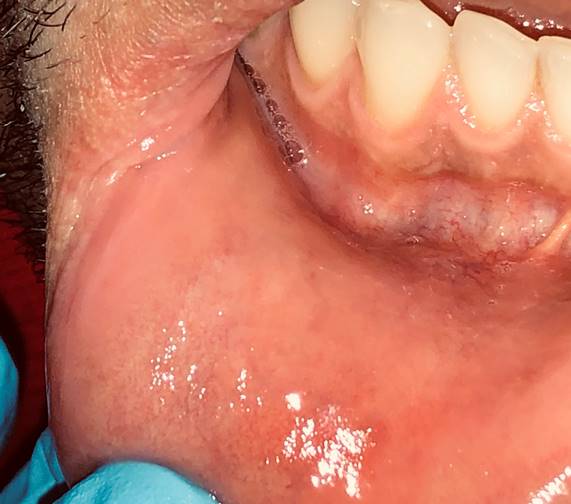

Al realizar el examen clínico se observó bermellón inferior reseco y fisurado, a nivel de mucosa labial inferior derecha úlcera de 3 x 4 cm, bordes muy indurados asociados a zonas erosivas y fondo cubierto por una seudomembrana amarillenta, dolorosa a la palpación y al roce con los dientes, refiere que inició más pequeña, pensó que se había mordido o lastimado, pero no sanó más bien ha crecido en 2 meses (Figura 1A). En cuello en el nivel III derecho presentaba dos adenopatías de 2 cm, tipo ovoide y dolorosas a la palpación, tiempo de evolución dos días. No se observaron alteraciones de contorno facial ni en piel (Figura 1B).

La lesión se curó dentro de una semana de tratamiento (Figura 2). Se realizó seguimiento con examen de sangre VDRL negativo a los 3, 6, 12 y 24 meses, refirió funcionalidad bucal y confort, está libre de lesiones.